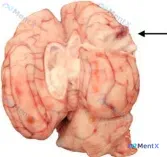

整理到一份犬死后检查的大体标本资料,先抛出来大家看看—— 标本是犬的大脑,右侧顶叶中背侧可见一个直径约1.5cm的病灶: - 局灶性、稍微隆起 - 质地软,整体偏白色 - 中心是红色的,还向脑实质深部延伸 早期只看影像的时候,思路其实有点偏,最后是靠尸检病理和微生物明确的。先不说结果,大家第一眼会先...